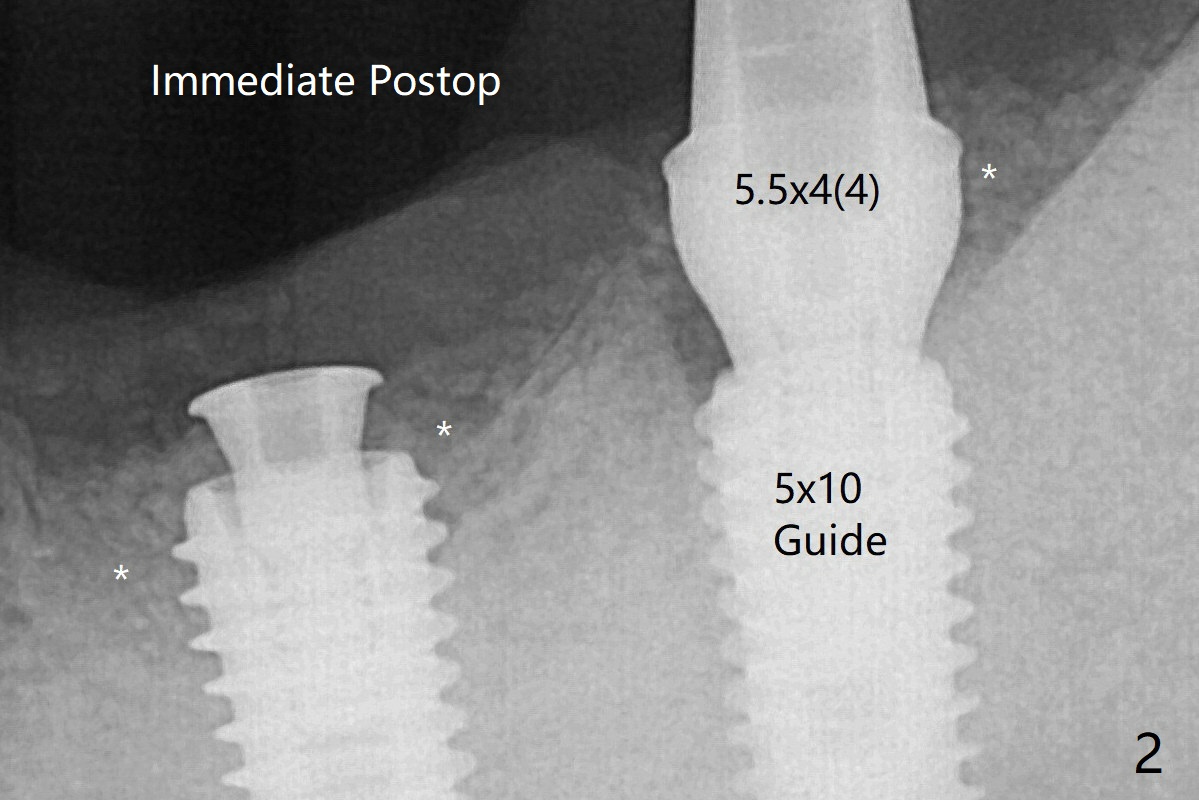

Guide vs. Free Hand Last Next